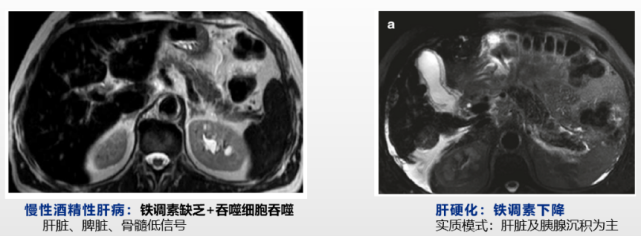

MRI可识别肝脏内铁的不均一分布,区分实质(脾信号正常,肝脏、胰腺和心脏信号低)和间质(脾信号下降,“黑脾”)铁过载。

原发性血色病1、2、3和4B型,铁常在肝细胞等实质细胞沉积,MRI表现为“黑肝”;4A因铁在巨噬细胞沉积而表现为“黑脾”。

贫血、输血铁超载时,铁在单核细胞沉积(脾脏、肝脏、骨髓等信号降低),后期铁可从巨噬细胞溢出而被肝脏、胰腺等实质细胞摄取,脾脏、肝脏、骨髓、胰腺MRI信号均降低。

肝硬化合并铁超载时,铁调素合成下降,铁主要在实质细胞沉积,MRI表现为肝脏、胰腺信号降低;酒精性肝病因铁调素下降及巨噬细胞吞噬铁增多,肝脏、脾脏信号均可降低。

但需注意的是,无论原发性血色病还是继发性铁超载,疾病后期当铁沉积严重时,铁在实质细胞和间质细胞均可沉积,MRI则难以区别原发性血色病及继发性血色病。

图片图8.慢性肝病MRI (引自讲者幻灯)